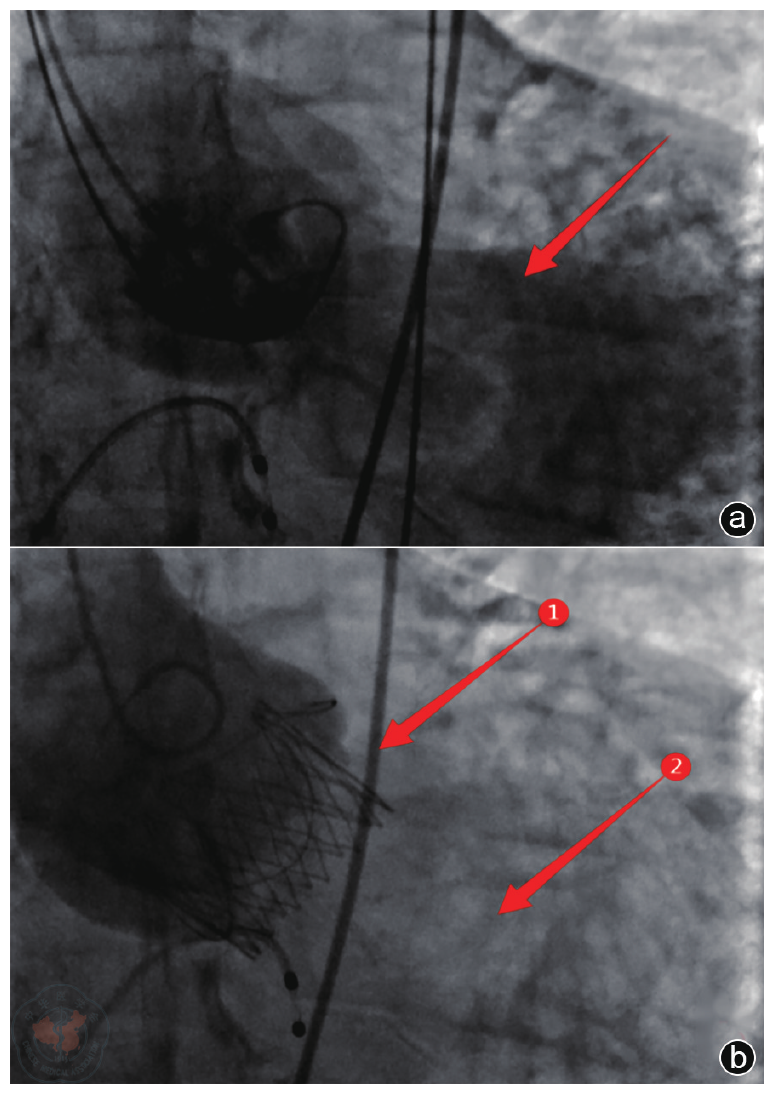

Methods The diagnosis and treatment data of one patient with severe AI admitted to the Air Force Medical Center on October 29, 2025, were retrospectively analyzed. Preoperative echocardiography was used to accurately assess valve structure (including number, morphology, echogenicity, etc.), the cause of regurgitation (including valve calcification, prolapse, perforation, annular dilatation, etc.) and its severity (including the ratio of regurgitant jet width to left ventricular outflow tract width, regurgitant area and length, Doppler spectra, etc.). Key aortic root dimensions were measured (including valve orifice area, aortic annulus, sinus of Valsalva, sinotubular junction, and ascending aortic diameters) to provide a basis for selecting the appropriate J-VALVE TF prosthesis size. Intraoperative ultrasound served as a real-time " navigation" system, guiding the entire process of device delivery and deployment, and providing immediate assessment of prosthesis position, function, and the presence of paravalvular leakage. Postoperative ultrasound served as the primary follow-up tool to evaluate prosthetic valve function and cardiac chamber reverse remodeling.

Results The patient experienced chest tightness and shortness of breath one year prior while lying flat at night. Symptoms could be induced by exertion or insomnia, lasted approximately one minute, and could be relieved by taking a deep breath. Echocardiography indicated: aortic developmental anomaly, aortic valve insufficiency with massive regurgitation, dilatation of the aortic sinus, and widening of the ascending aorta. Based on clinical presentation and echocardiographic findings, the patient underwent TAVR using the J-VALVE TF valve system. Intraoperative ultrasound provided real-time guidance during the delivery and deployment of the J-VALVE TF valve, monitoring the deployment process and the relative position of the delivery system. It was used to assess potential impacts on the mitral valve and coronary ostia before deployment and to evaluate prosthetic valve function after deployment. Postoperative assessment focused on the presence of paravalvular leakage, cardiac function, and the recovery of cardiac chamber geometry.